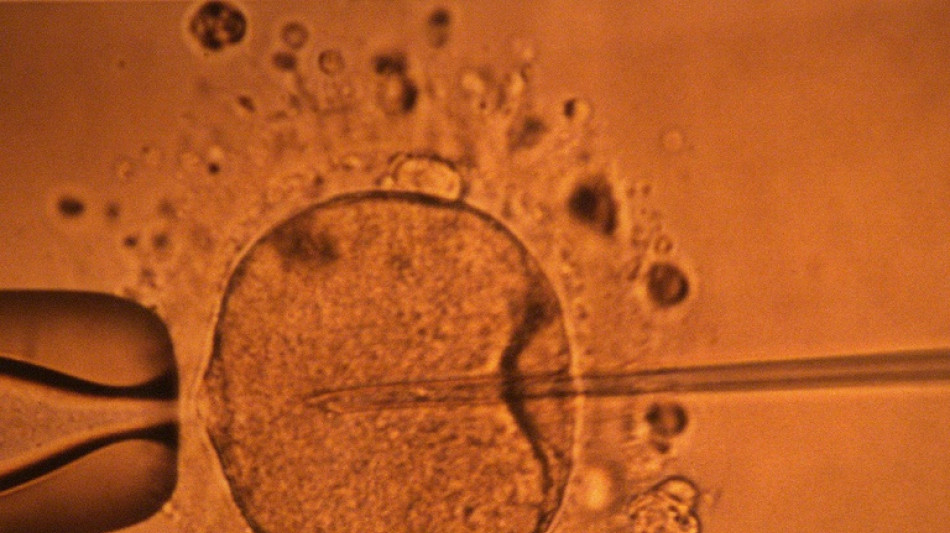

Une étude appuie l'hypothèse d'un déclin mondial de la concentration en spermatozoïdes / Photo: MARCEL MOCHET - AFP/Archives

La concentration en spermatozoïdes, l'un des facteurs de la fertilité masculine, a nettement baissé à travers toute la planète au cours des dernières décennies, avance une vaste étude publiée mardi.